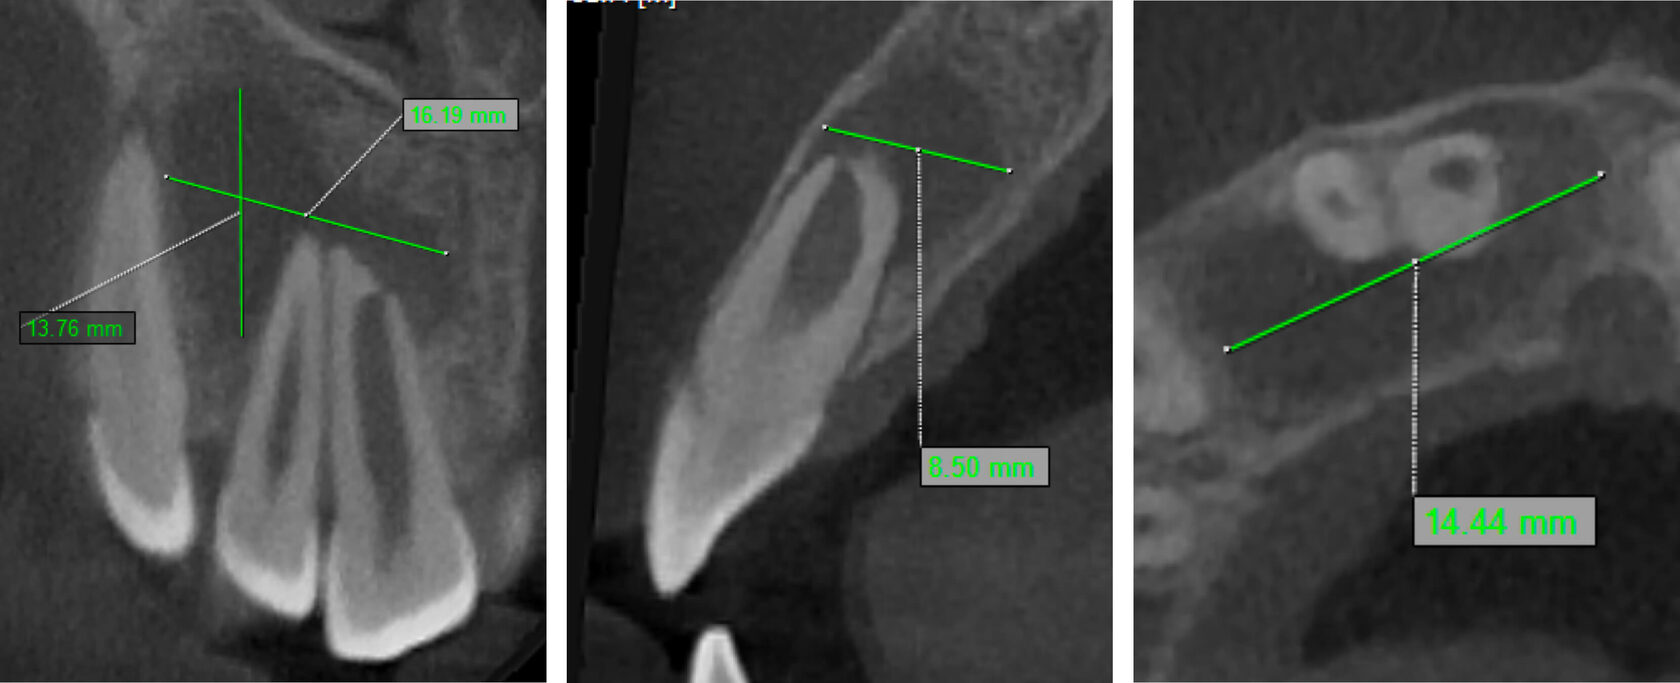

2. Зуб 11 девитален, апикальный периодонтит с обширной деструкцией костной ткани, зуб 12 витален. (Фото 2,3,4)

3. В первое посещение сформирован эндодонтический доступ, выполнена медикаментозная очистка корневого канала без применения инструментов, временная обтурация препаратом на основе гидроксида кальция сроком на 2 недели. (Фото 5,6)